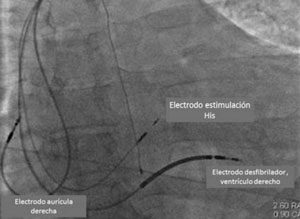

Ya han comenzado estudios que comparan MHH y TRC clásica vía seno coronario en pacientes con las indicaciones clásicas de TRC, lo que ha determinado un gran entusiasmo ante la posibilidad de lograr la resincronización en pacientes con indicación de TRC sin necesidad de ubicar un electrodo en el VI y con un procedimiento mucho más sencillo que el de TRC clásico (Figura 5) (Figura 6).

Figura 6: Imagen radioscópica de un paciente en el que se realizó implante de CDI bicameral con marcapaseo de His. Modificado de referencia 43.